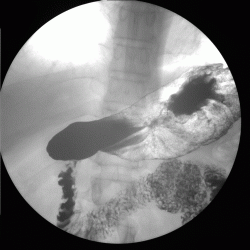

пациента беспокоят боли в области эпигастрия.Выполнена ФГДС вот результат. Пищевод свободно проходим с нормальным просветом и слизистой. Розетка кардии эластиная, смыкается не полностью. В желудке умеренное количество жидкости и слизи с примесью желчи. Слизистая оболочка розовая, отечна, складки нормальной ориентации, утолщены, извиты, эластичность стенок желудка и перистальтика сохранены во всех отделах. В ср/3 тела желудка, на задней стенке определяется язвенный дефект 1,5*0,8 см округлой формы, с припднятыми отечными краями, с конвергенцией складок слизистой, в дне фибрин. Окружающая слизистая отечна, разрыхлена,застойна. При щипковой биопсии подслиистый слой плотный. Антральный отдел, привртаник, луковица и постбульбарный отдел ДПК без особенностей.

ЗАКЛЮЧЕНИЕ: Гипертрофический гастрит. Язва ср/3 тела желудка, maligna ?

Ну и на последок дообследован рентгенскопически.

По поводу самого обследования. Контраст в нашей клинике- "Бар Випс", ну а газообразующая смесь, как обычно , сода+лимонная кислота.

А сама методика как везде. Исследование выполнено на аппарате США фирмы"general electric" presicion.

Ничего на самом деле необычного. Просто давно было не мной замечено:пациента надо повернуть так,как этого необходимо для установки диагноза.

Может,все-таки учитывая подозрение специалиста ФГС на малигнизацию, и был направлен в рентгенкабинет.Все же оценить перистальтику,наличие ригидных участков ,считаю, можно лучше с помощью R-скопии. А как известно ригидность -один из признаков злокачественности.

3.Вы совершенно правы по поводу рентгенологического исследования (перистальтики, ригидности и пр.). Должен отметить, как это не прозвучит парадоксально, что 20 лет тому, когда рентгенологические исследование все еще оставалось ведущим исследованием в гастроэктерологии (хотя эндоскопия уже была и "набирала силу"), мы исследовали пациентов более тщательно, используя максимум возможностей от данного исследования, которое и теперь может дать "фору" многим конкурирующим исследованиям. Но многое забыто или не используется. Совершенно забыта (или не используется?) фармакодиагностика, применение которой, в своё время решало многие диагностические вопросы, да и многое другое...

Красиво, как по книжке. Поделитесь секретом с молодым спецалистом о методике выполнения двойного контрастирования. ПОЖАЛУЙСТА!

Уважаемая Людмила Александровна! Классика жанра! Все рентгенологические симптомы язвы желудка налицо!